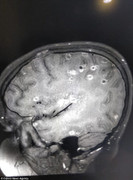

Một bé gái 8 tuổi bị đau đầu tê liệt, co giật và lên cơn động kinh, sau khi nhập viện cả người nhà và bác sĩ đều sửng sốt khi phát hiện 100 trứng sán dây trong não cô bé.